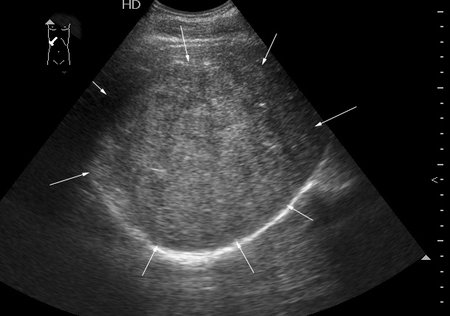

Молодой человек, наркоман, поступил в хирургическое отделение с подозрением на абсцесс печени.

Жалобы на высокую температуру, слабость.

Сонограмма печени:

Год назад при УЗИ в печени находили образование больших размеров.

Что-то не укладывается именно ультразвуковая картирка в абсцесс печени.